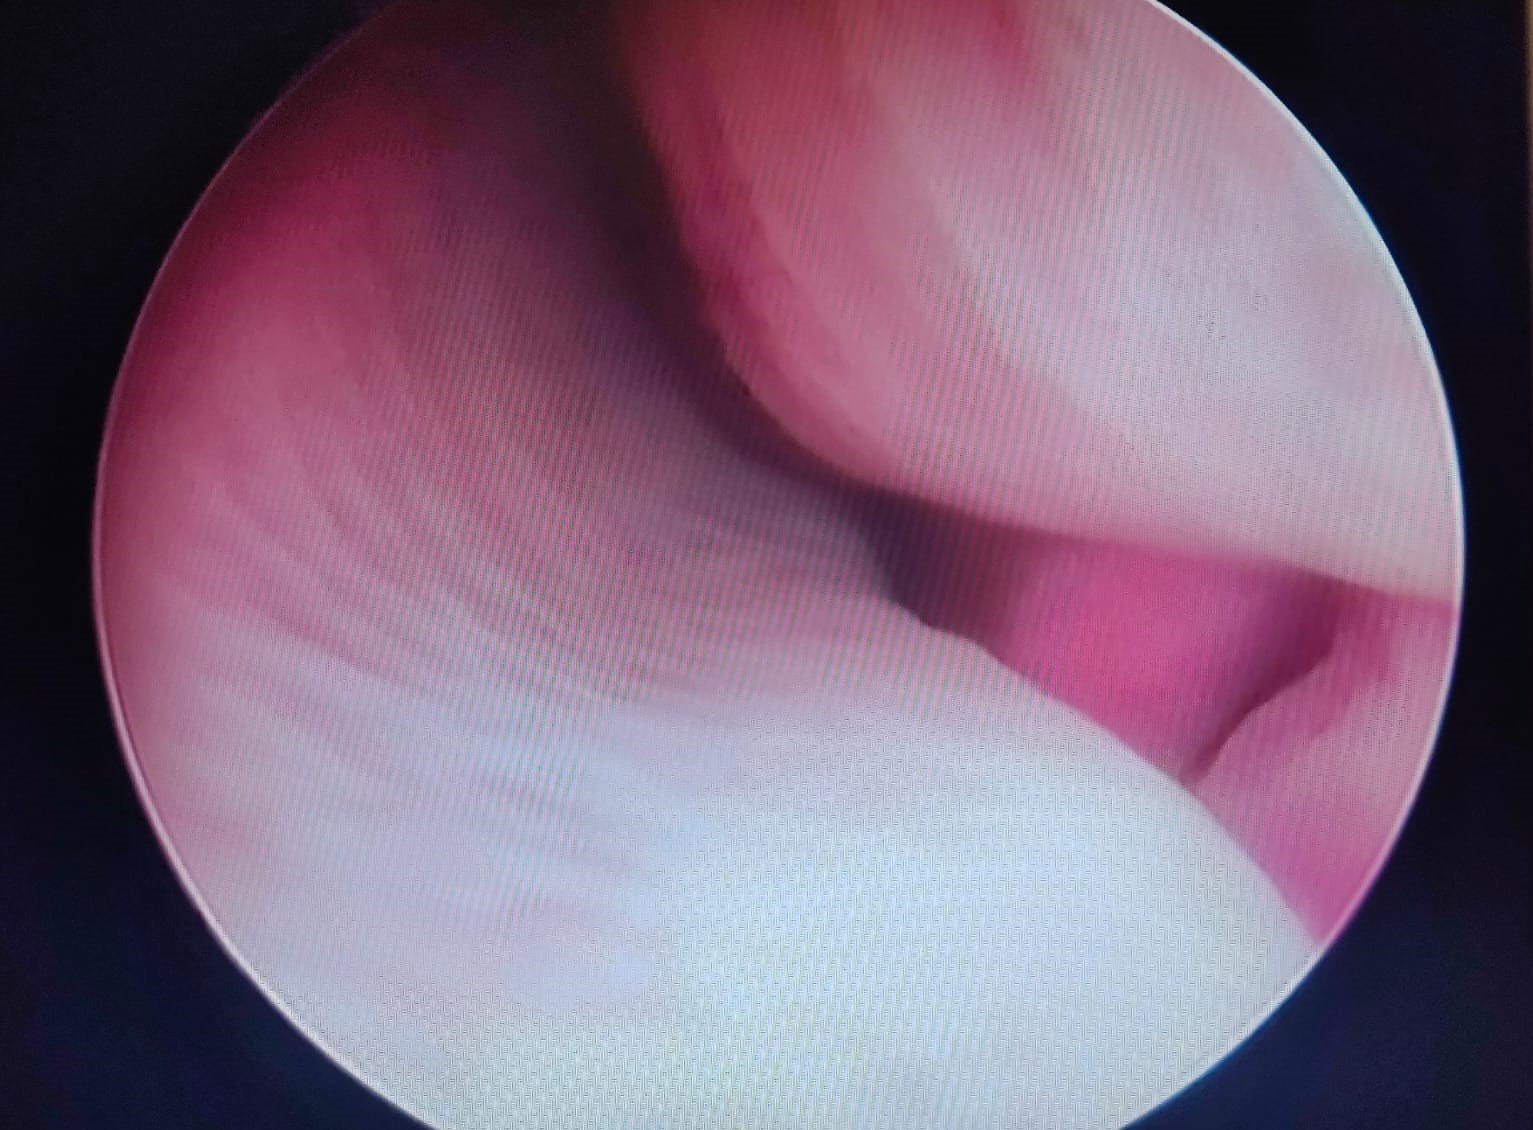

La video otoscopia è un ausilio diagnostico fondamentale nelle indagini del canale auricolare in corso di otiti e corpi estranei. Tramite questo strumento si rende possibile l’asportazione di materiale patologico all’interno dell’orecchio e l’esame completo del canale auricolare e del timpano. La tecnica viene eseguita in anestesia generale per ottenere il miglior risultato senza dolore per il paziente

Orecchio dopo lavaggio